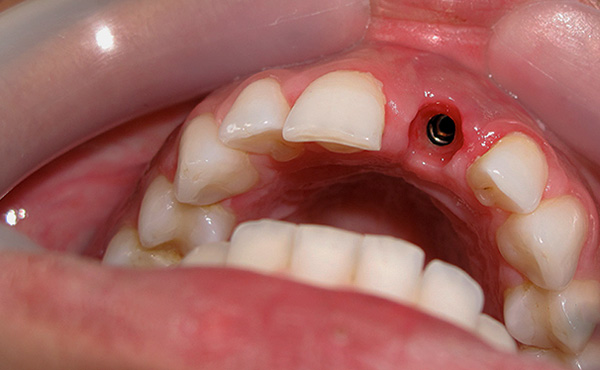

E sotto la foto mostra farfalla protesica (in realtà, questa è una protesi temporanea, tuttavia, molte persone la usano come permanente):